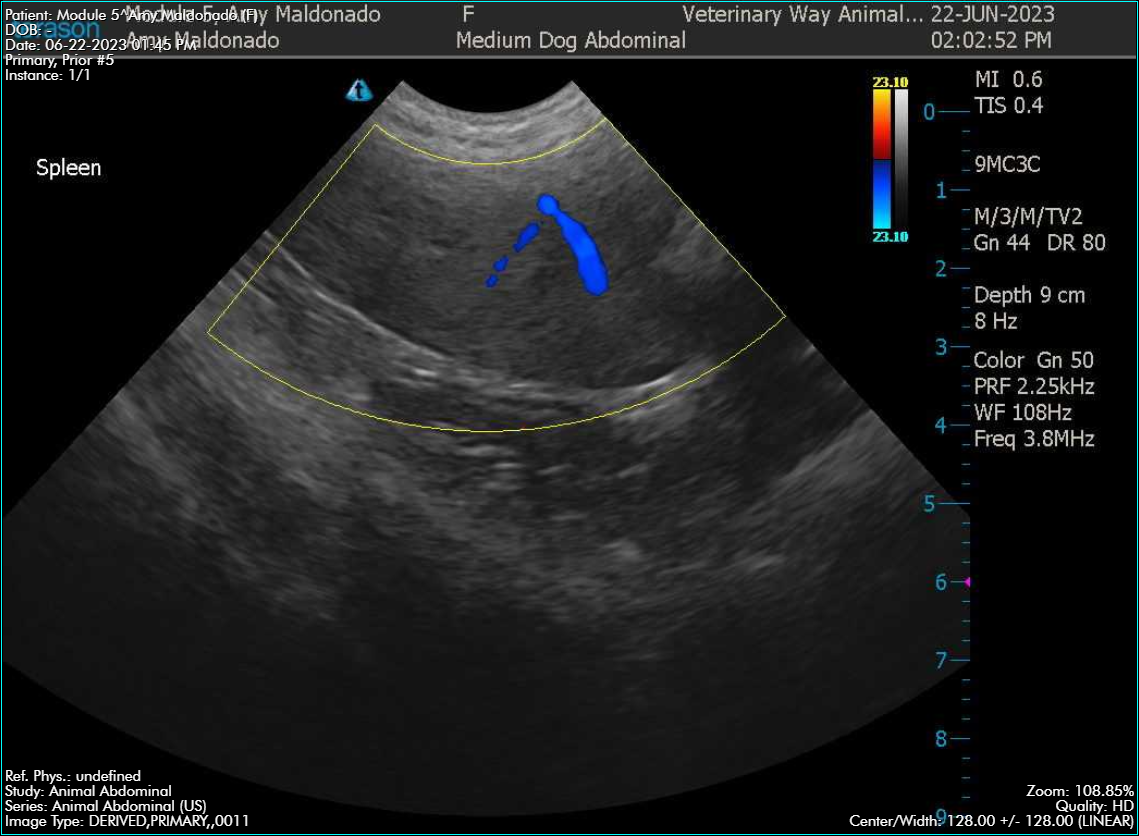

Unlike standard X-rays, ultrasound allows our team to see the texture and internal structure of organs in real-time, providing a deeper look at your pet’s health without invasive procedures.

- Precision & Compassion: From routine abdominal scans to more complex diagnostic cases, our ultrasound services help us deliver precise, compassionate care every step of the way.

- Organ Evaluation: Screening for tumors, bladder stones, or enlarged organs.